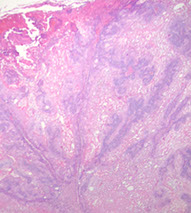

Basal cell carcinoma (BCC)

NON-lethal skin cancer; locally invasive but almost never mets

- MC of ALL cancers

- MC in skin exposed areas of body

~ 90% bwt hairline and upper lip

~ 5% recurrence

- can look like dermatitis clinically or actinic keratosis

Rolled edges w central ulceration

- pearly papules w telangiectasias; palisading nuclei

~ form thymidine dimers due to sun exposure

3 criteria for dx: palisading, clefting and nesting

- myxoid change around edge of tumor, that can cause clefting artifact

- "Basal cells stroma" - changes with dilated vessels, lymphocytes and mucin around BCC

- irritated BCCs can get squamoid differentiation, probably do not need to mention unless is very diffuse

- infiltrating / sclerosing / morpheaform (all the same) may be more locally aggressive form of BCC, that may need to be more aggressively treated, can have perineural invasion if infiltrates really deep, and have higher rates of recurrence

- fibroepithelioma of Pinkus is probably just a form of BCC and should be treated as such

- can have areas of pleomorphism in BCC, if it merges into more normal looking BCC, probably do not need to worry or treat differently

- BCC can also blend into a part of the tumor that has large zones with fluffy granular cells that is called "granular cell variant of BCC" which usually transitions into areas of more normal looking BCC - can look like melanoma

- also can have clear ceell variant of BCC that should also transition into more normal looking BCC

- amyloid in BCC is probably just a breakdown product of degenerative keratin and does not mean that the pt has systemic amyloidosis (can be seen in other adnexal tumors

- may have stromal retraction around tumor

BCC can be pigmented and look like melanoma clinically

IHC: (+) CD34 (may be negative), BCL-2 (strong and diffuse)

- negative CK20+ Merkel cells (negative at least in tumor islands)

Tx: Moh's micrographic surgery

- if BCC is superficial pattern, dermatologist may choose to treat with topical agents

Nodular BCC with nesting, clefting and pallisading

Squamous differentiation in BCC

Superficial pattern BCC

Morpheaform / sclerosing / infiltrative BCC